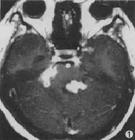

2.MRI表現:

結核性腦膜炎好發生於腦底部,表現為腦底部的軟腦膜和蛛網膜下腔的廣泛炎症。滲出和粘連、增厚。T1加權像顯示腦基底池信號增高,T2加權像上信號更高,增強MRI後顯示蛛網膜間隙異常強化。結核性腦膜炎常引起3種併發症:結核性腦膜腦炎、腦梗塞和交通性腦積水。結核性腦膜腦炎好發於腦底、丘腦和基底節附近的腦實質,T2加權可見上述部位腦實質內有斑片狀高信號強度改變,其內可散在小點片狀的低信號影為乾酪性壞死,增強後有邊緣強化。腦梗塞好發在大腦中動脈供血區,梗塞灶較少,T2加權像上可見小片狀高信號強度影散布在基底節和題項葉腦實質內。由於腦基底池的結核炎症滲出,易波及中腦導水管引起阻塞。MRI圖像可見導水管以上腦室擴張積液。增強後導水管內可見小條狀強化病灶。

結核瘤T1加權像呈低信號,包膜為等信號。T2加權像信號不均,包膜為低或略高信號。結核瘤鈣化在T1和T2加權像均為低信號或不顯示。